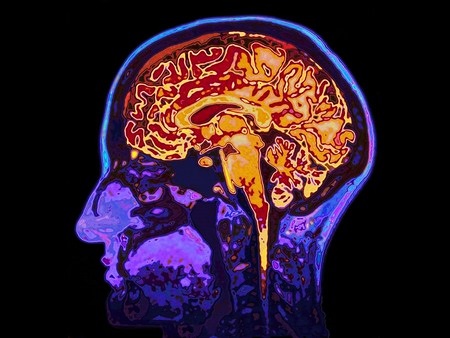

Расположение мозга в голове видно на срезе.

Головной мозг, наряду со спинным, образует ЦНС. Мозг расположен в черепе, защищен от повреждения жидкостью, которой заполнена черепная полость, цереброспинальной жидкостью. Строение головного мозга человека очень сложное – оно включает кору, делящуюся на 2 полушария, которые функционально различаются.